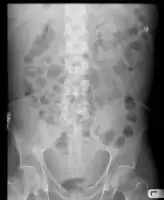

Diagnosis

Routine complete blood count (CBC), basic metabolic profile, liver enzymes, and coagulation should be performed. Most experts recommend a diagnostic paracentesis be performed if the ascites is new or if the person with ascites is being admitted to the hospital. The fluid is then reviewed for its gross appearance, protein level, albumin, and cell counts (red and white). Additional tests will be performed if indicated such as microbiological culture, Gram stain and cytopathology.[6]

The serum-ascites albumin gradient (SAAG) is probably a better discriminant than older measures (transudate versus exudate) for the causes of ascites.[10] A high gradient (> 1.1 g/dL) indicates the ascites is due to portal hypertension. A low gradient (< 1.1 g/dL) indicates ascites of non-portal hypertensive as a cause.

Ultrasound investigation is often performed prior to attempts to remove fluid from the abdomen. This may reveal the size and shape of the abdominal organs, and Doppler studies may show the direction of flow in the portal vein, as well as detecting Budd-Chiari syndrome (thrombosis of the hepatic vein) and portal vein thrombosis. Additionally, the sonographer can make an estimation of the amount of ascitic fluid, and difficult-to-drain ascites may be drained under ultrasound guidance. An abdominal CT scan is a more accurate alternate to reveal abdominal organ structure and morphology.